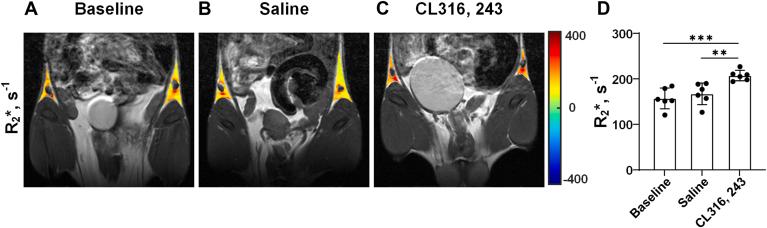

White adipose tissue (WAT) browning is considered a promising strategy to combat obesity and related metabolic diseases. Currently, fat-water fraction (FWF) has been used as a marker for the loss of lipids associated with WAT browning. However, FWF may not be sensitive to metabolic changes and cannot specifically reflect iron-regulated metabolism during browning. Here, we report a noninvasive preclinical imaging approach based on iron content detected by R∗ mapping to assess in vivo WAT browning in mice. In this study, we investigated the browning of inguinal white adipose tissue (iWAT) induced by long-term CL-316,243 (CL) drug stimulation in mice. We quantified the changes in R∗, FWF, uncoupling protein 1 (UCP1) expression, and iron content. The iWAT of all mice was dissected for H&E staining and immunohistochemistry for the absorbance of UCP1 and iron content. In in vivo experiments, a significant increase in R∗ and a decrease in FWF were observed in iWAT after 7 days of CL administration compared with the saline-treated and the baseline groups. Accordingly, in ex vivo experiments, UCP1 expression and the total iron content in iWAT significantly increased after 7 days of CL stimulation. By pooling all mice data, the UCP1 expression level of iWAT and iron content was found to be highly correlated with R∗ and inversely correlated with FWF. Taken together, R∗ may serve as a potential imaging biomarker for assessing WAT browning, which provides a new diagnostic and therapeutic evaluation tool for metabolic diseases.

白色脂肪组织(WAT)褐变被认为是对抗肥胖及相关代谢性疾病的一种有前景的策略。目前,脂肪水分数(FWF)已被用作与WAT褐变相关的脂质损失的标志物。然而,FWF可能对代谢变化不敏感,并且不能特异性反映褐变过程中铁调节的代谢。在此,我们报告一种基于通过R∗映射检测铁含量的非侵入性临床前成像方法,以评估小鼠体内的WAT褐变。在本研究中,我们研究了长期使用CL-316,243(CL)药物刺激诱导的小鼠腹股沟白色脂肪组织(iWAT)的褐变。我们量化了R∗、FWF、解偶联蛋白1(UCP1)表达和铁含量的变化。解剖所有小鼠的iWAT进行苏木精-伊红(H&E)染色以及针对UCP1吸光度和铁含量的免疫组织化学分析。在体内实验中,与生理盐水处理组和基线组相比,CL给药7天后iWAT中的R∗显著增加,FWF降低。相应地,在体外实验中,CL刺激7天后iWAT中的UCP1表达和总铁含量显著增加。通过汇总所有小鼠的数据,发现iWAT的UCP1表达水平和铁含量与R∗高度相关,与FWF呈负相关。综上所述,R∗可作为评估WAT褐变的潜在成像生物标志物,为代谢性疾病提供了一种新的诊断和治疗评估工具。